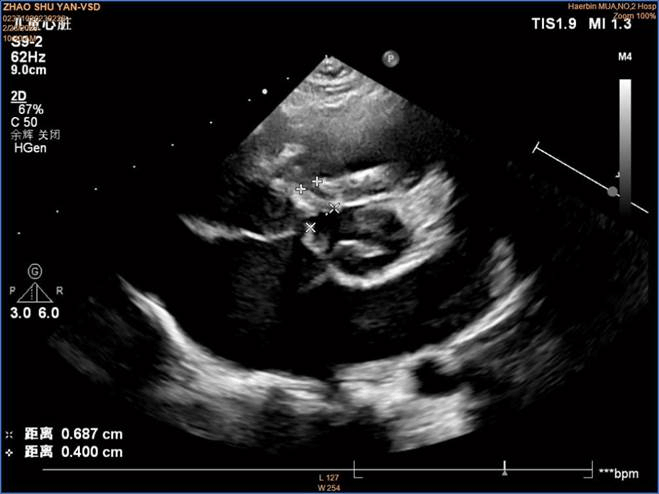

术前彩超

入院后经过全面检查发现心脏杂音,心脏超声证实室间隔缺损,缺损直径约为4.4 mm,确诊为室间隔缺损合并膨出瘤。自然闭合的可能性几乎没有,符合介入封堵手术治疗指征。